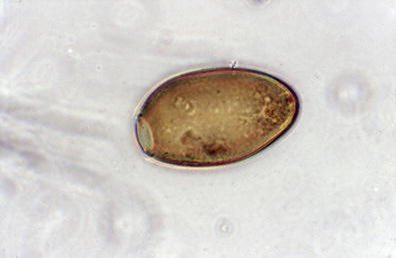

وبعدها آخر شيء البيض الغير ناضج الكتكوت هَذا بيطلع مع الفضلات وبعد ماطلع البيض يحتاج ماي عشان يكمل دورة حياته واذا لقى الماي بينضج أكثر ومابيصير الحين بيضة غير ناضجة بيصير miracidia